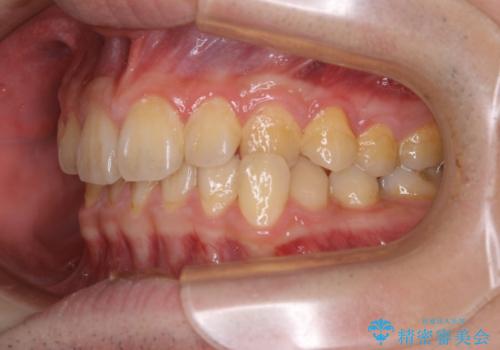

人生で初めてのクリーニングということもあり、プラークや歯石が大量に付いていました。それにより、歯茎の腫れもあり出血も多かったです。これから矯正をスタートしていくため、歯ブラシ指導を行いホームケアを頑張ってもらっています。